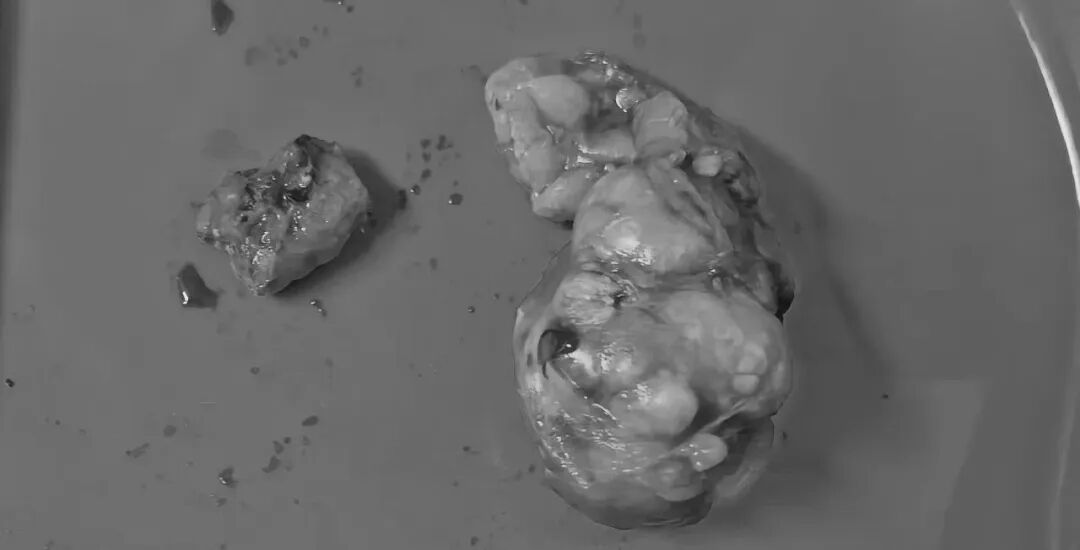

左肾肿瘤

病理诊断:乳头状细胞癌